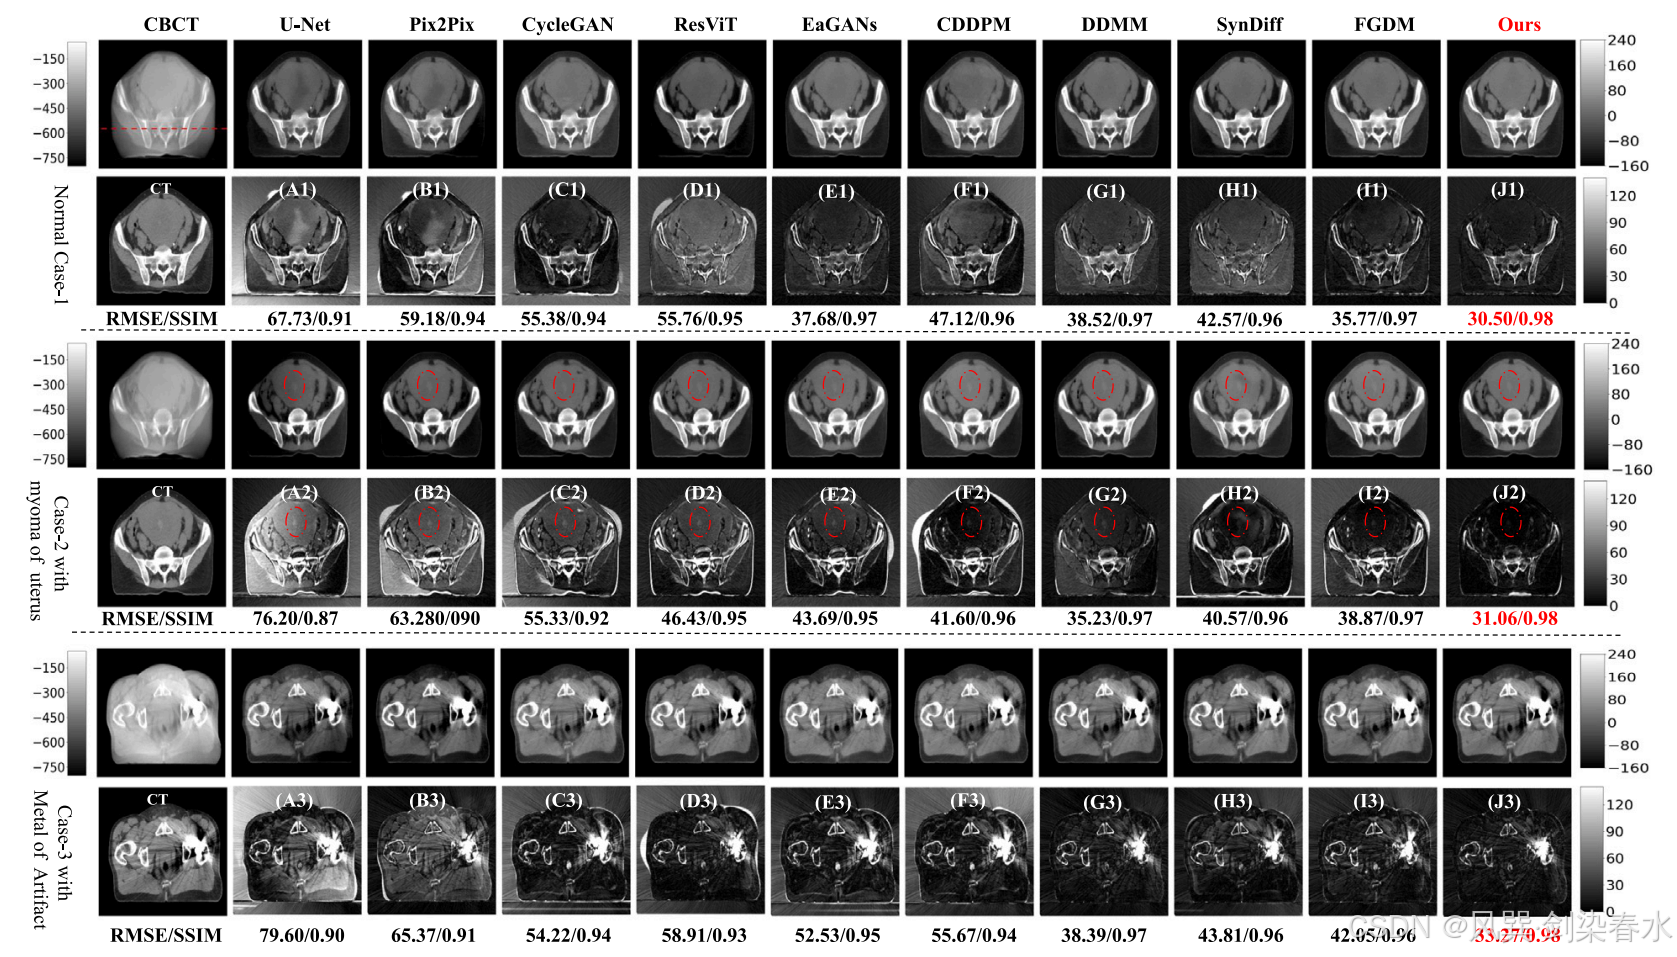

Figure 2 | 内部骨盆测试数据集可视化:这里选取了三个典型案例:一个来自健康个体;一个来自患有子宫肌瘤的个体,用红色虚线椭圆标出;另一个来自髋关节植入金属假体的个体。(A1-J1)、(A2-J2)和(A3-J3)分别是 CT 图像与相应预测 sCT 图像之间的绝对差异。CBCT 的显示范围为 [−800,−50] HU,而 CT 和 sCT 的显示范围则为 [−160,240] HU;

Figure 3 | 图2 所示的一维强度分布是通过沿红色虚线扫描得到的:图中的插图清楚地显示了与其它方法相比,所提出的方法具有优越的性能: